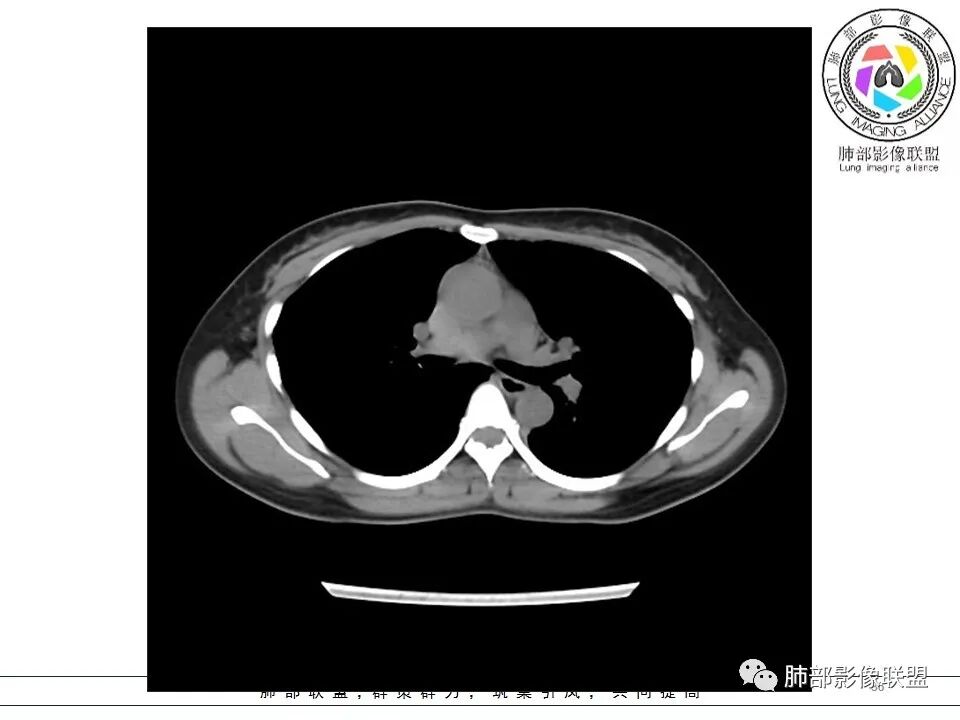

女,38岁,无症状,胸片体检发现两肺可疑病灶。

?其母亲有肺大泡,2017年手术。影像学特点:两肺胸膜下多发的大小不等囊状气腔,壁很薄或无可见的囊壁,小囊的边界比较清楚,大囊的形态比较怪异,以两下肺为著。考虑肺组织细胞增生症,鉴别肺淋巴管肌瘤病。

其母亲有肺大泡,2017年手术。

BHD主要影像表现特征:    1、两肺内肺囊肿:80%以上的BHD患者会出现肺内囊肿,且倾向于基底部近胸膜下分布,特别是纵膈侧肺膜下,囊肿形状不规则、囊肿可大可小,肺内囊肿多毗邻肺下动脉或静脉近端,胸部CT上囊肿分布和特点对诊断有提示意义。    2、继发自发性气胸:BHD患者发生气胸风险是正常人的5倍,BHD患者的气胸发生率约为 1/4,气胸复发率则高达59%。   3、肾肿瘤:(常为双侧性、倾向于嫌色细胞组织学亚型)   4、皮肤表现(为面、颈部纤维性毛囊瘤、毛盘瘤)